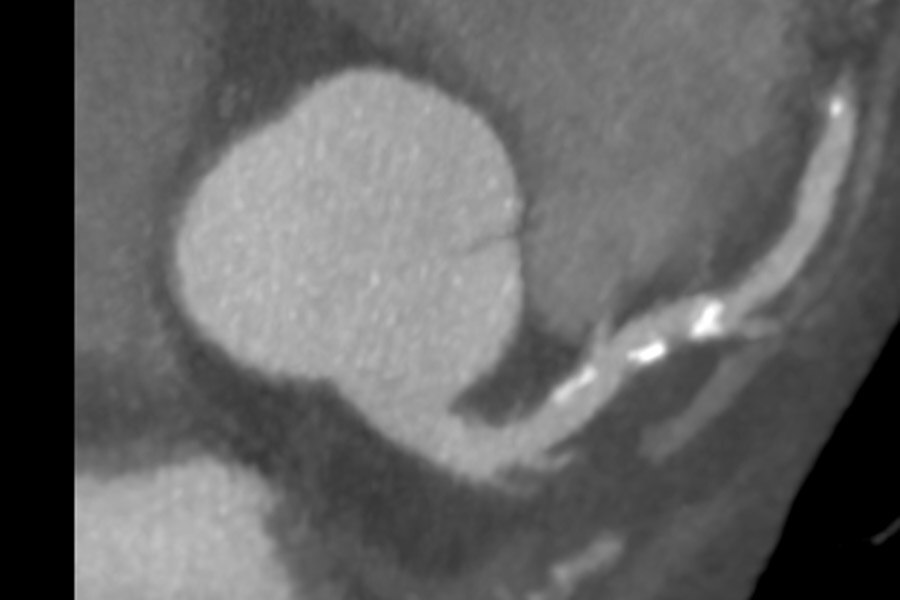

Visualization of the lumen of stents on 53-year-old male, 51 BPM, BMI 31